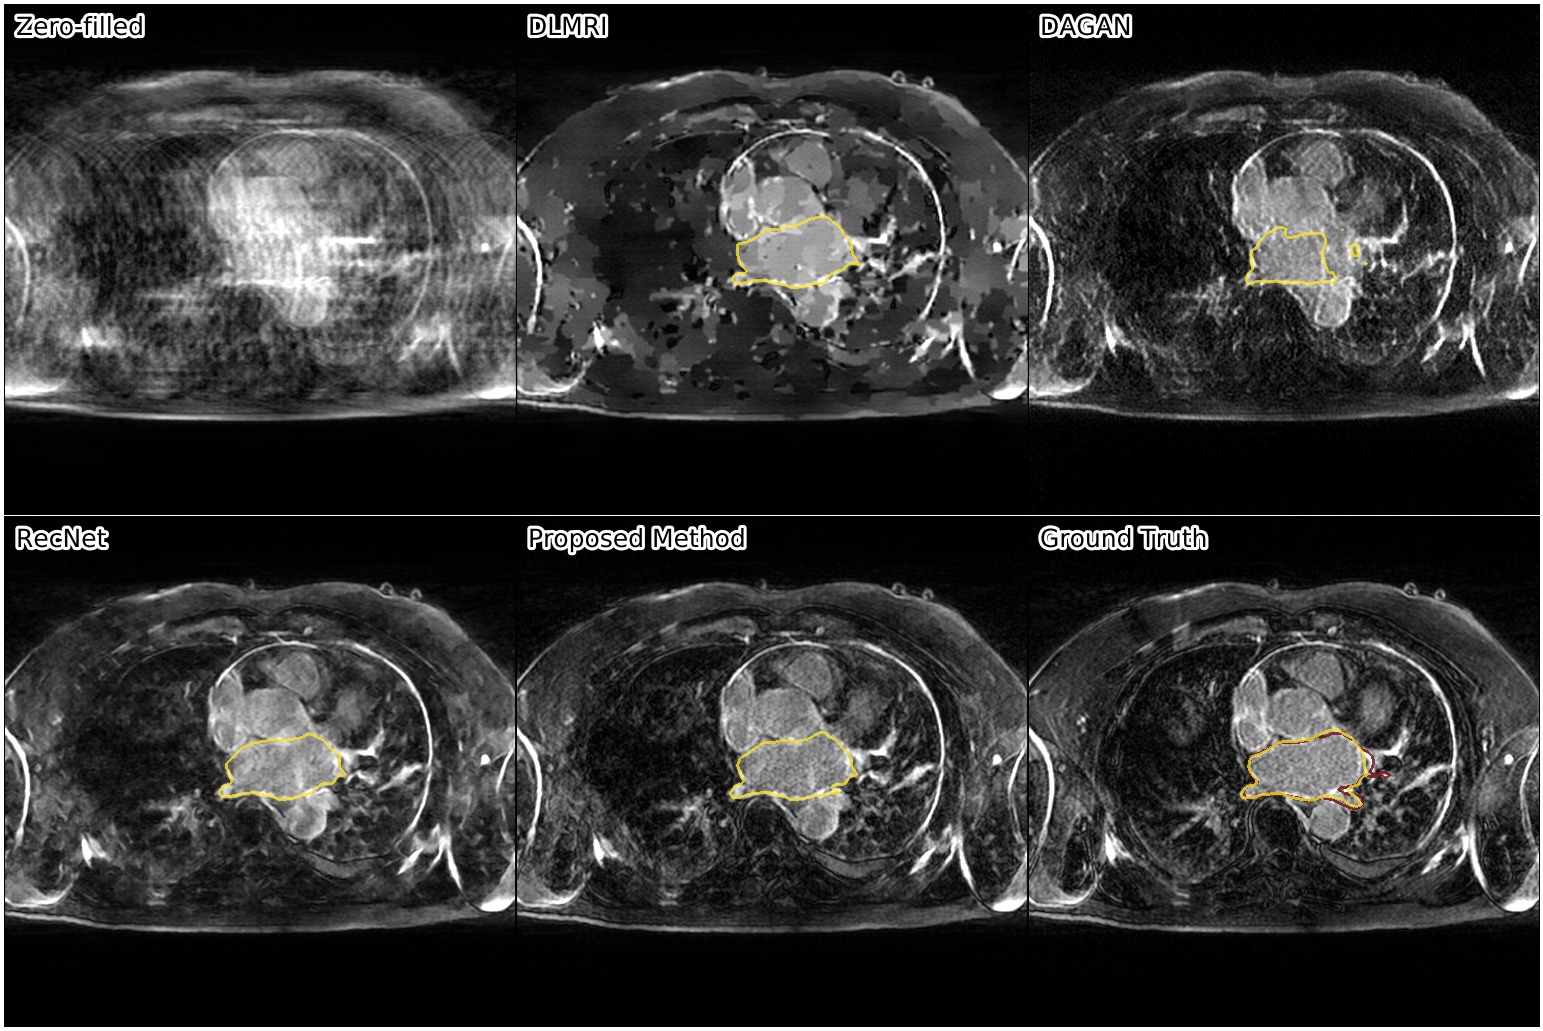

We show the results of our evaluation in Table 1, and a sample reconstruction in Figure 2. RecNet performed best in terms of PSNR, which is expected as its training objective directly corresponds to this metric, but its reconstructions were over-smoothed. DLMRI had the lowest MOS, with its reconstructions showing heavy oil paint artifacts. DAGAN, combining MSE loss with a visual loss function without any further precautions, suffered from low PSNR. While its reconstructions also looked sharp, they were noisy and often displayed aliasing artifacts, which was reflected in a lower MOS compared to our method. Our proposed approach achieved significantly444Significance determined by a two-sided paired Wilcoxon signed-rank test at . higher mean opinion score than all other methods, while still maintaining high PSNR. Reconstructions obtained by our method appeared sharper with better contrast. Moreover, our method achieved the highest SIS close to segmentation performance on the ground truth data, which indicated that the segmented objects were clearly visible in the reconstructed images.

The following images show more samples for 8-fold undersampling. For each of the seven patients of the test set, a random slice showing the left atrium was selected. The contour of the predicted segmentation of left atrium is shown in yellow, the contour of the ground truth segmentation in red.